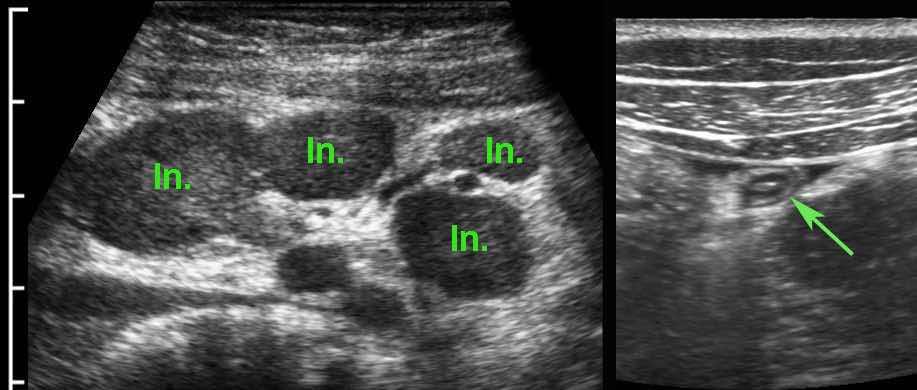

Ở bệnh nhân 16 tuổi này với đau hố chậu phải, các hạch bạch huyết mạc treo to được bao quanh bởi một ít mỡ đang viêm (*) là dấu hiệu siêu âm duy nhất và không xác định được ruột thừa.

CT xác nhận các hạch to (đầu mũi tên), nhưng phát hiện thêm ruột thừa đang viêm (mũi tên), xuất phát từ manh tràng ở vị trí sâu trong tiểu khung.

Bệnh nhân trẻ bị viêm ruột thừa cấp thường có hạch bạch huyết mạc treo to thứ phát.